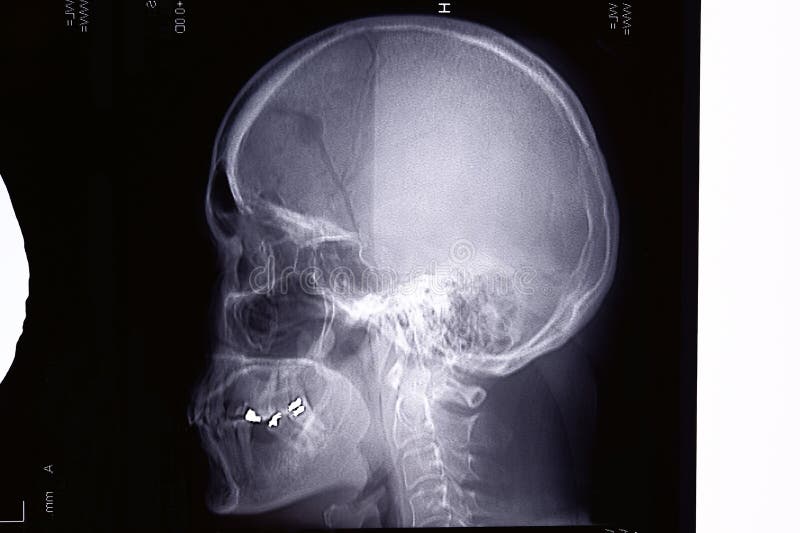

Lesione Cerebrale Traumatica Traumi Avvelenamento Manuali Msd Edizione Professionisti

Trauma Cranico Wikipedia